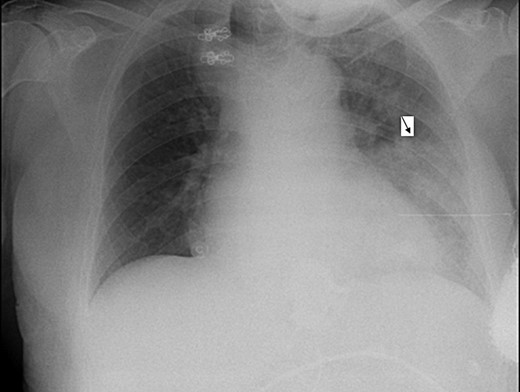

Electrocardiogram was remarkable for Q waves in leads I, aVL and V6. Chest X-ray (CXR) demonstrated a marked esophageal distention with an air fluid level (Figs 1 and 2).

Lateral CXR view demonstrates dilated esophagus and fluid air level (E), contrast medium-filled inflatable inner cuff (C), connecting silicone tube (T) and subcutaneous sutured radiopaque access port (P).